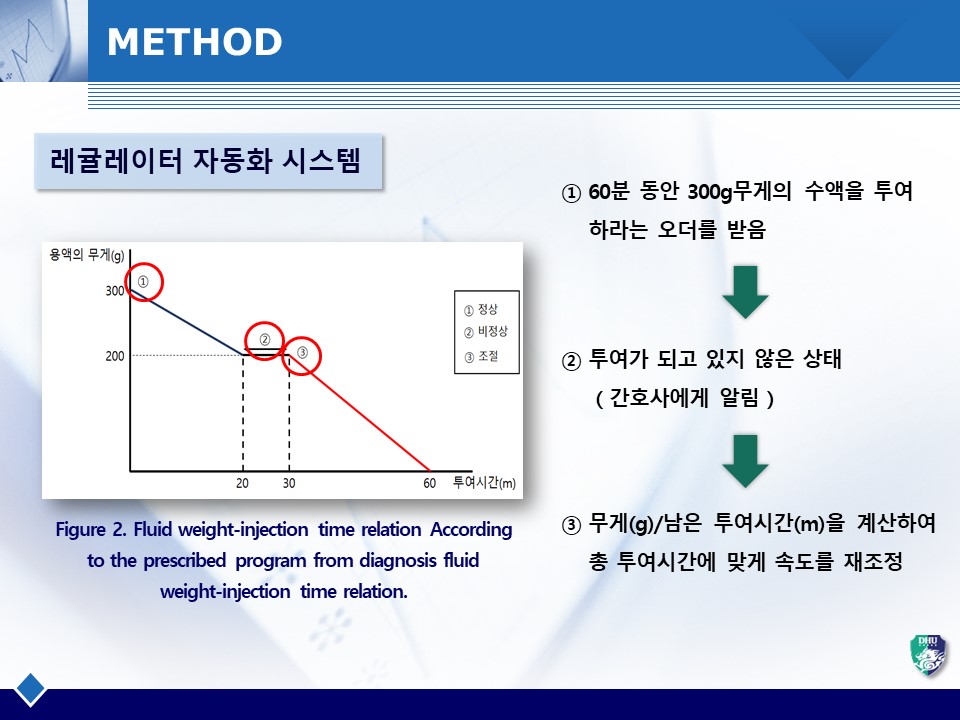

수액투여 시 의료사고를 방지하고 정확한 양의 수액을 투여하기 위한 자동화 및 모니터링 시스템을 개발함. 스마트 수액 거치대를 통해 실시간 수액의 중량변화를 모니터링하고, 오토-레귤레이터가 자동으로 유량을 조절함. 수액 거치대와 오토-레귤레이터를 설계 및 제작하고 주입오차 테스트를 통해 정밀도를 측정함.